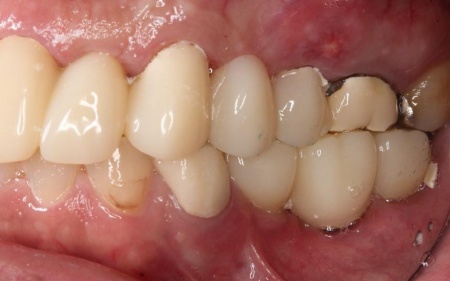

治療後

他院で治療を行った左下奥歯3本のインプラントは、土台をそのまま活かして人工歯だけ作り直し、噛み合わせを調整します。

左下奥歯1本、右下奥歯2本に装着されていた古い被せ物はすべて外し、ジルコニアクラウンと交換しました。